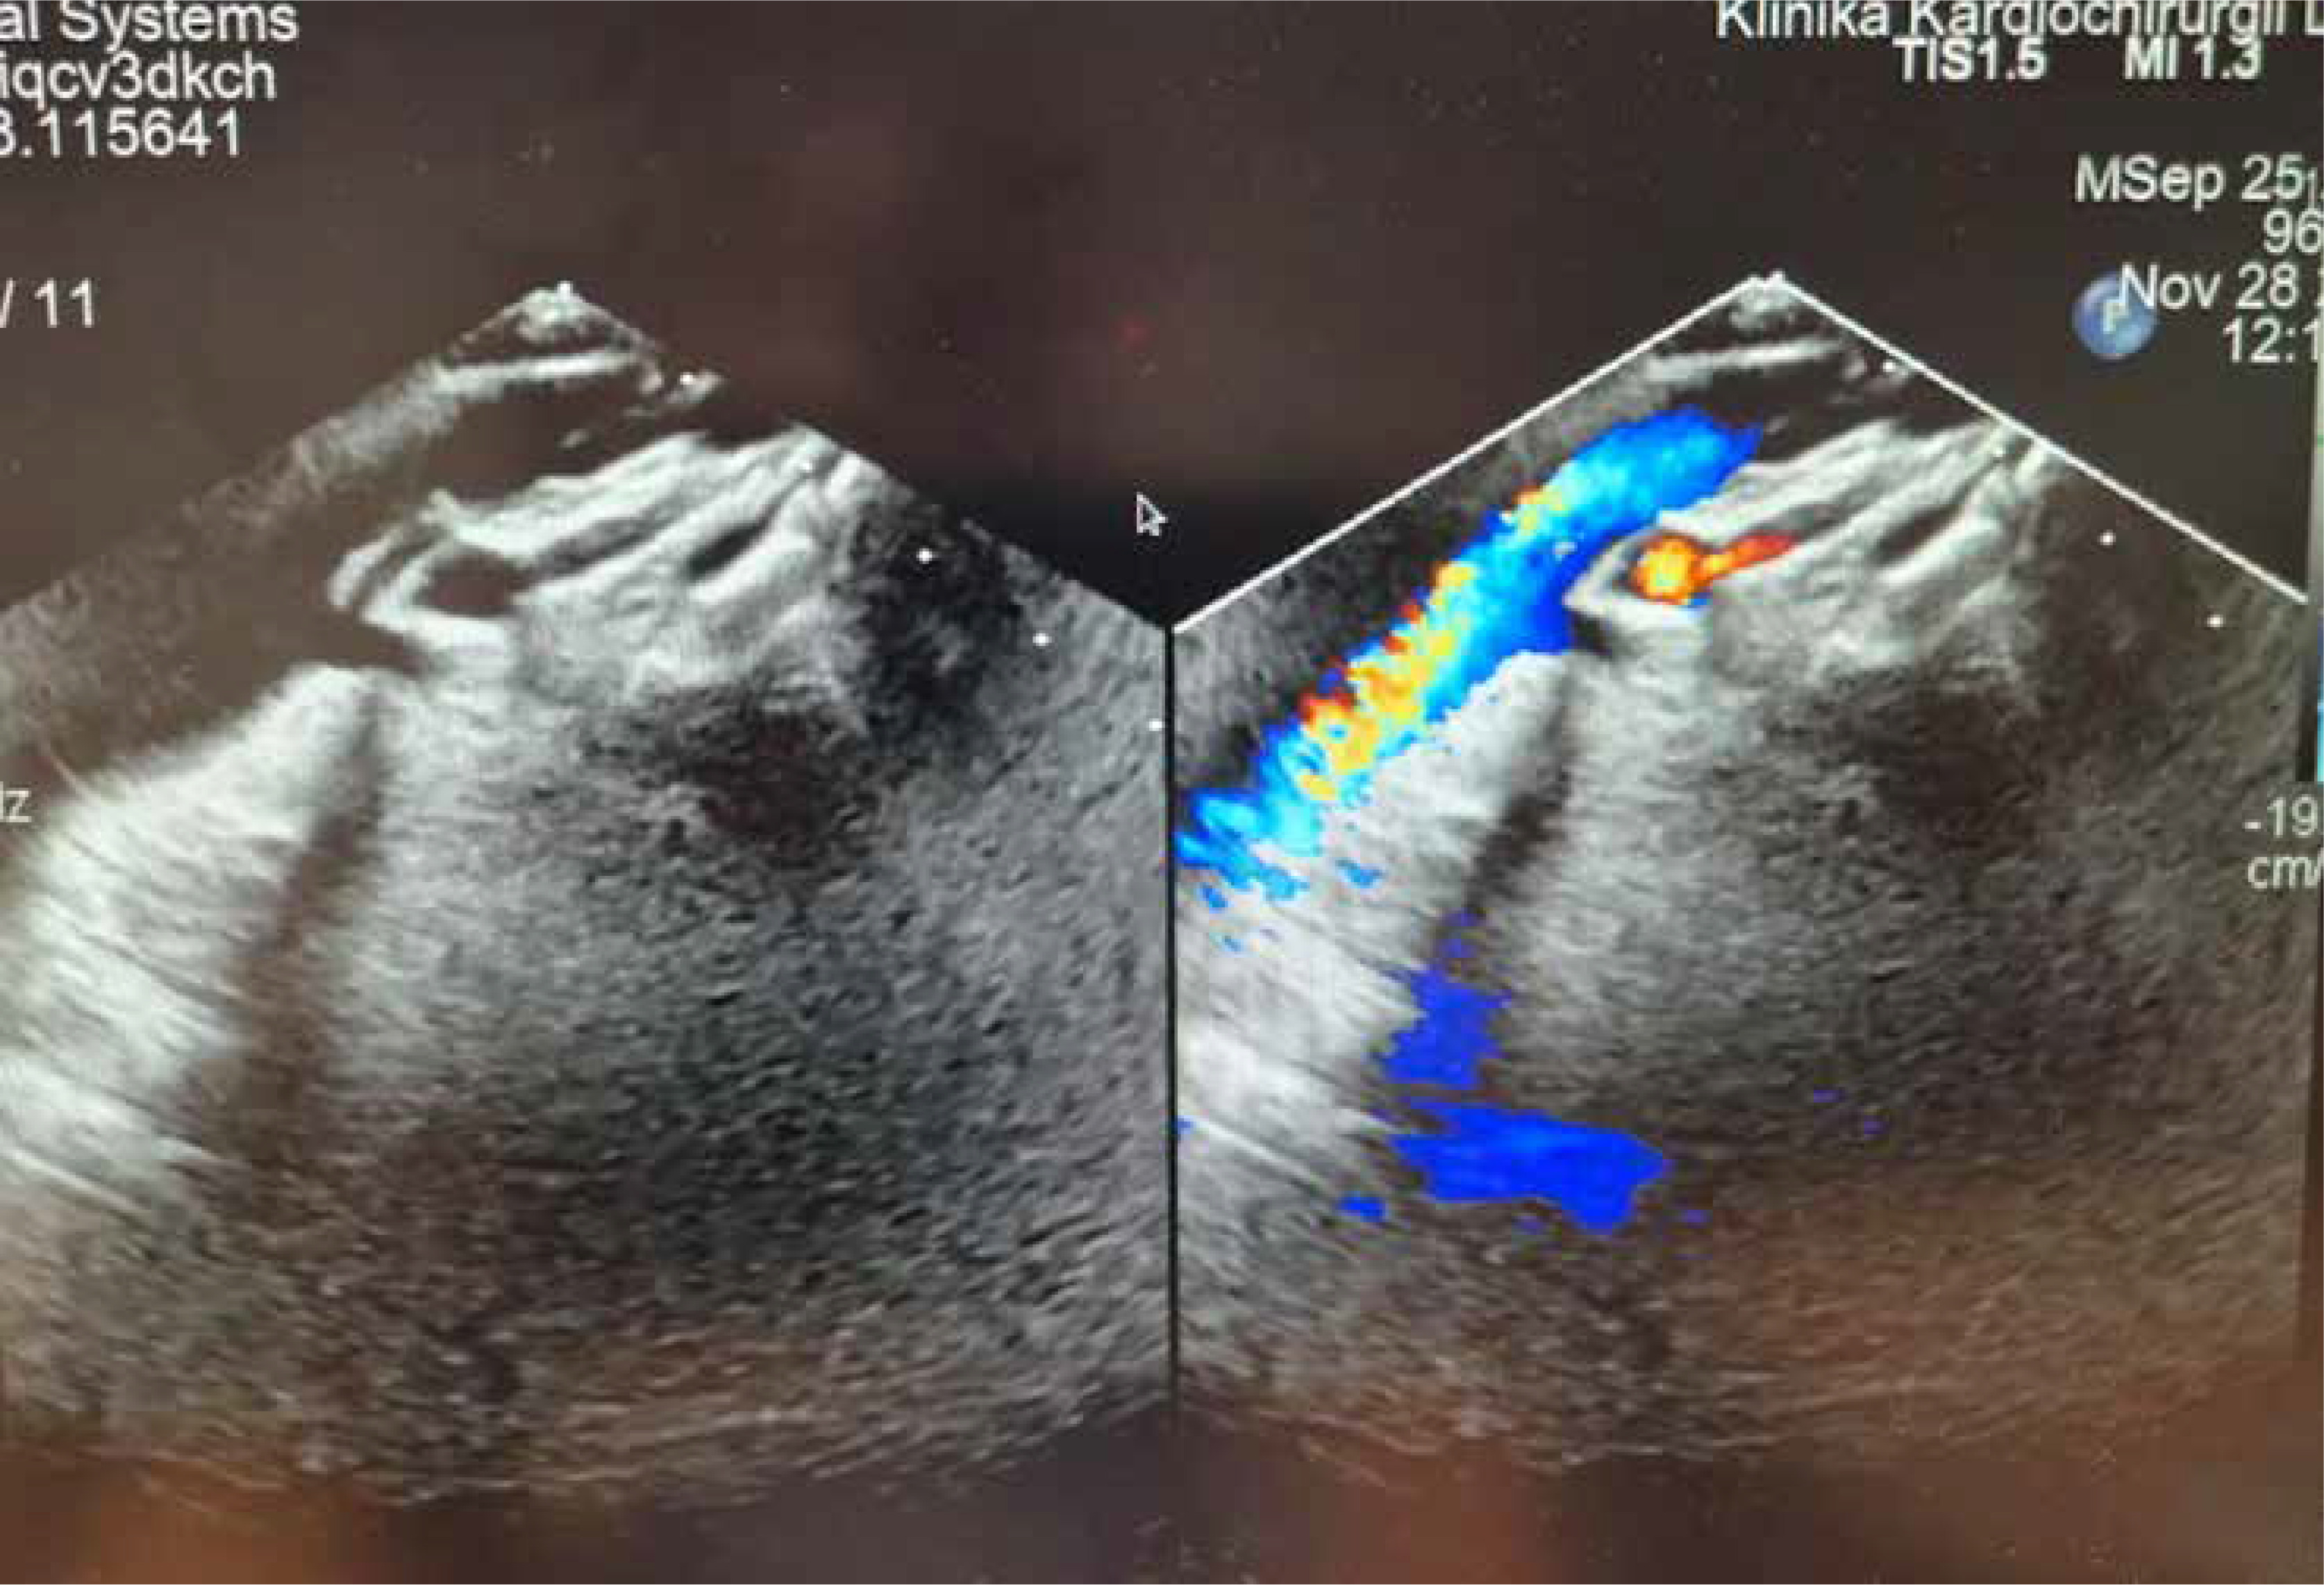

The patient recovered uneventfully, with oxygen saturation improving to 90% in the early postoperative period. He was discharged home on the 10th postoperative day with patent Hraska anastomosis (Figure 7) and mild systolic and diastolic right ventricular dysfunction on pharmacologic treatment.

Figure 7

Echocardiographic picture of patent Hraska anastomosis between the left brachio-cephalic (innominate) vein and right atrial appendage. The colour Doppler flow through the 8 mm reinforced polytetrafluoroethylene (Gore-Tex) vessel anastomosis is visible